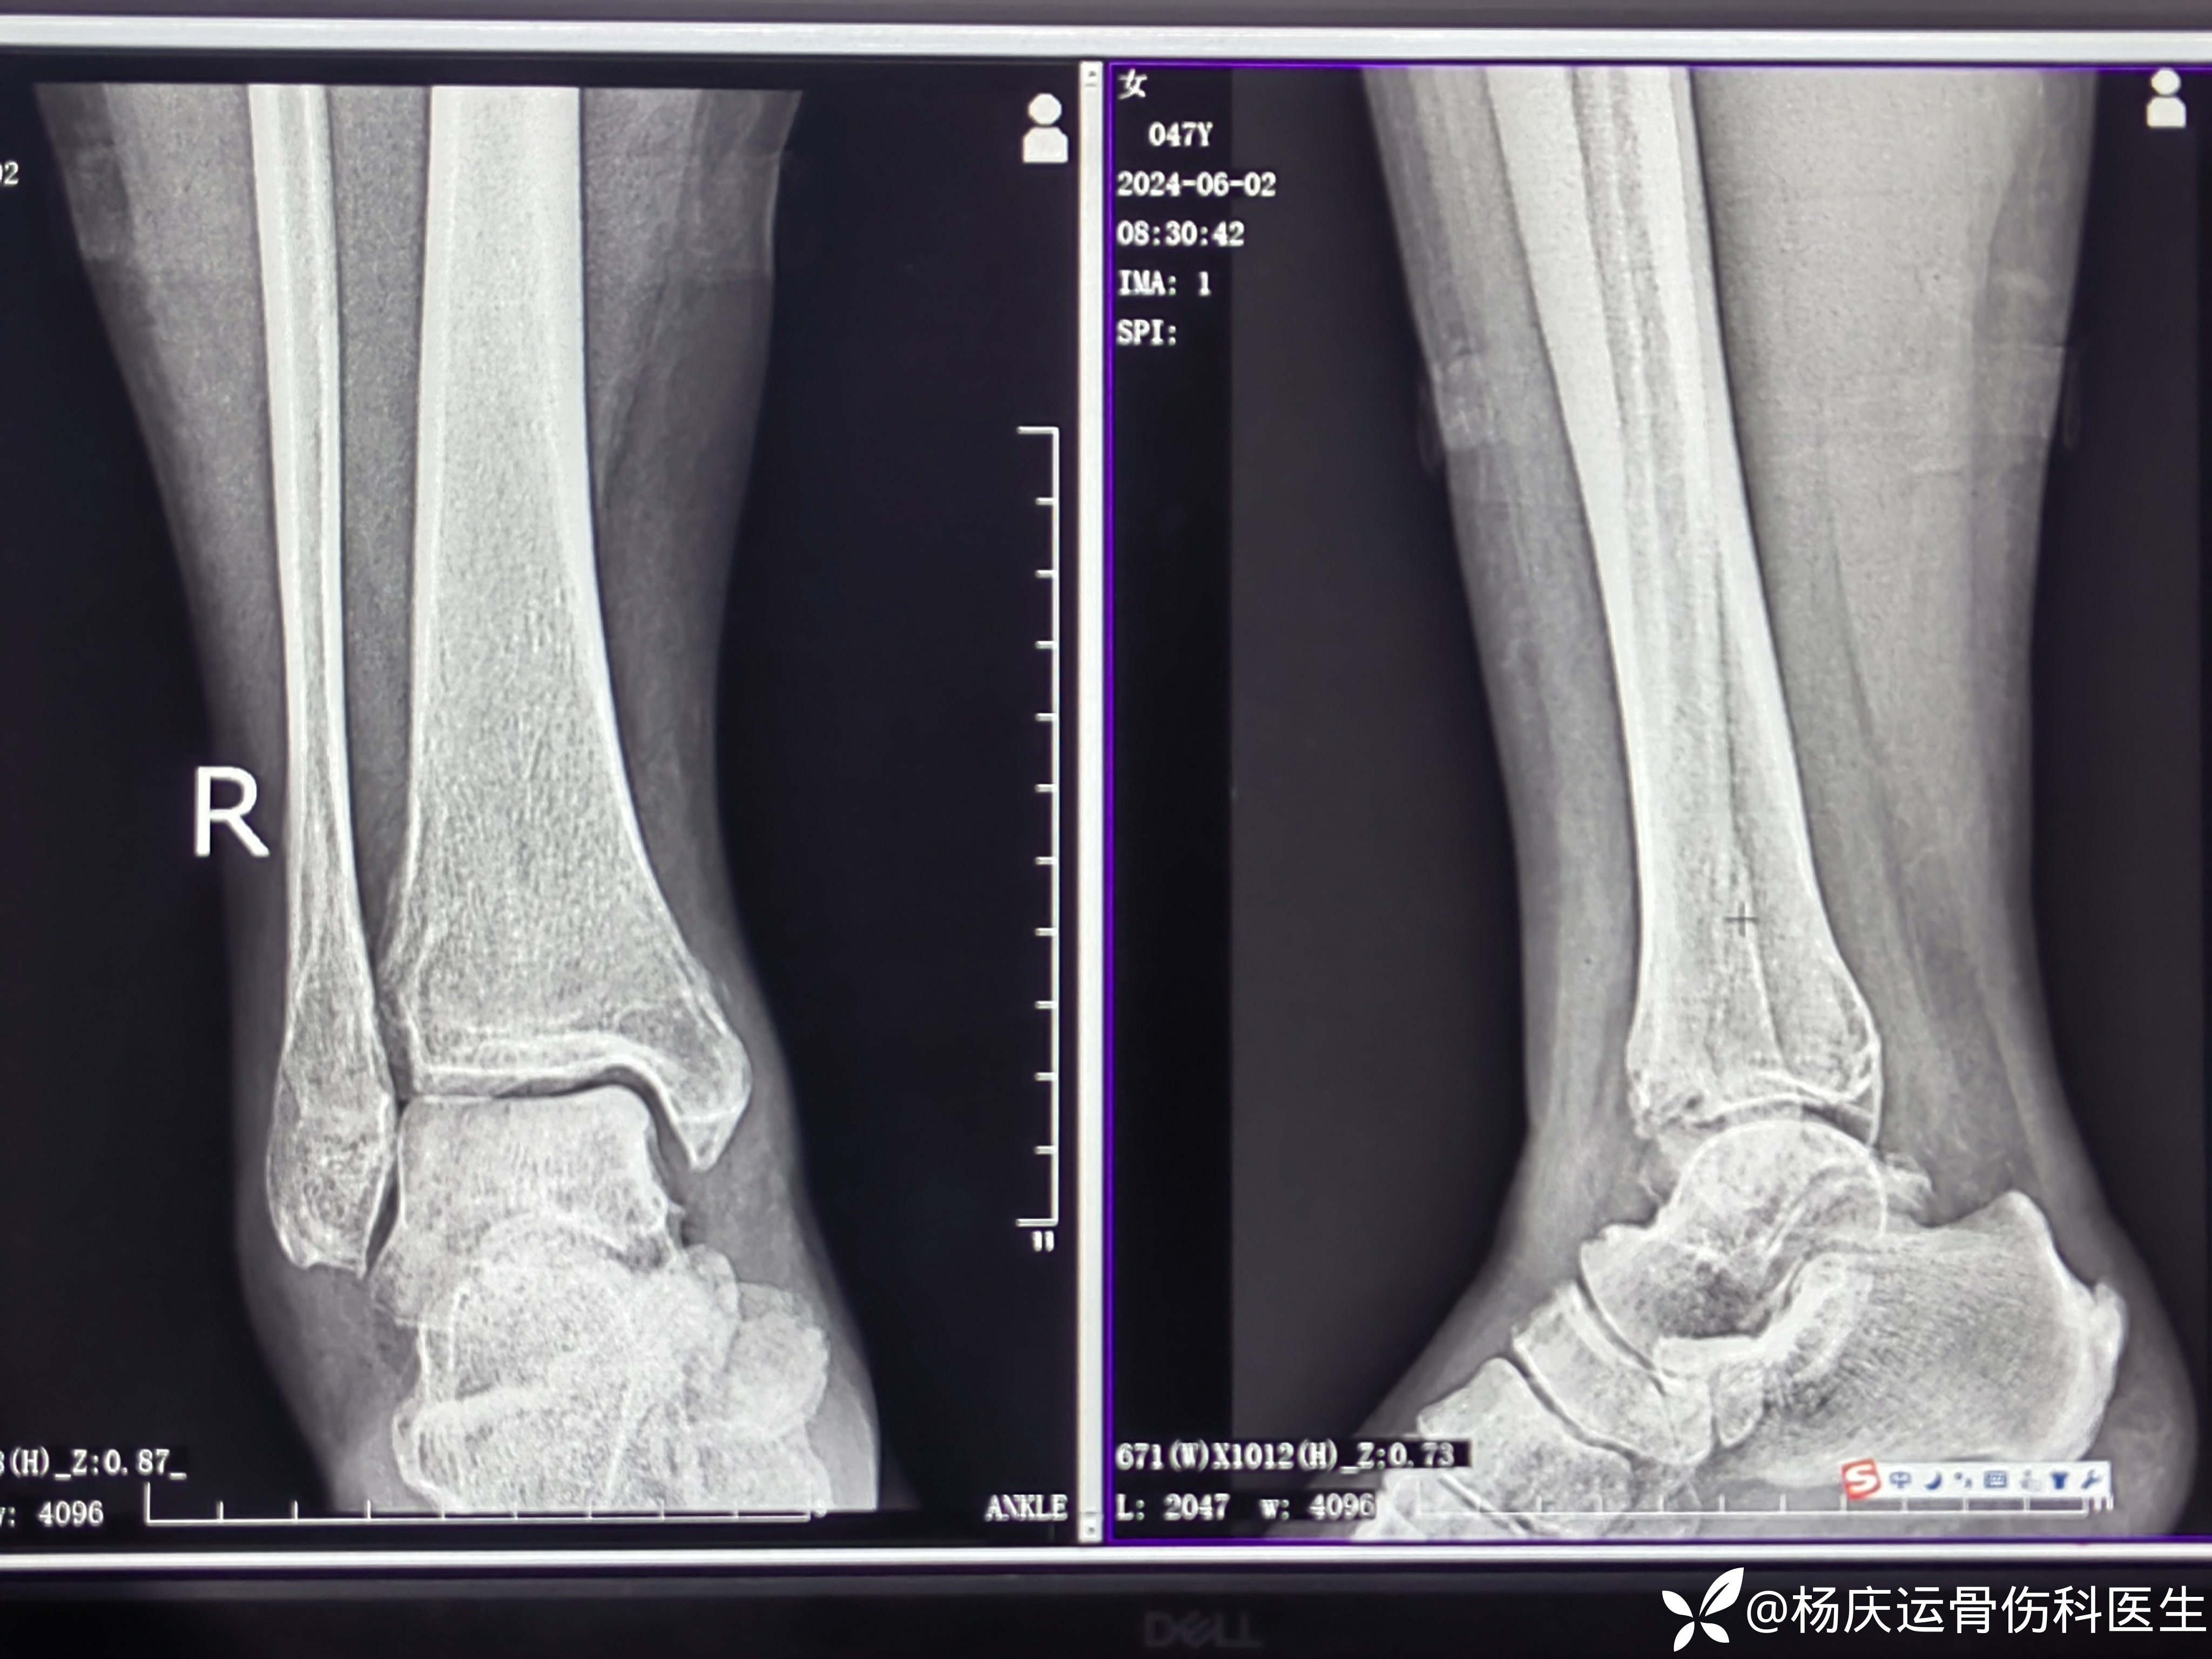

55天复查,更换行走石膏拄拐轻负重行走。

4个月复查

10个月复查